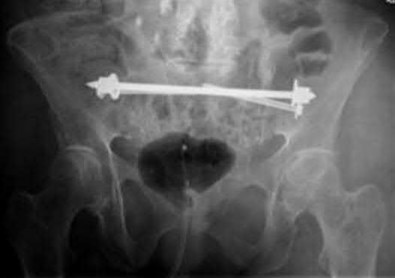

A 35-year-old male sustains an anteroposterior compression (APC) type II pelvic ring injury.

During anterior ring fixation via an ilioinguinal approach, massive hemorrhage is encountered posterior to the superior pubic ramus. Which anomalous anatomical connection represents the classic 'corona mortis'?

Explanation

The 'corona mortis' (crown of death) refers to a vascular anastomosis between the obturator and external iliac (or inferior epigastric) vascular systems. It is located posterior to the superior pubic ramus at a variable distance (average 5-6 cm) from the symphysis pubis and can cause life-threatening hemorrhage if inadvertently disrupted during anterior pelvic ring surgery (ilioinguinal or Stoppa approaches).